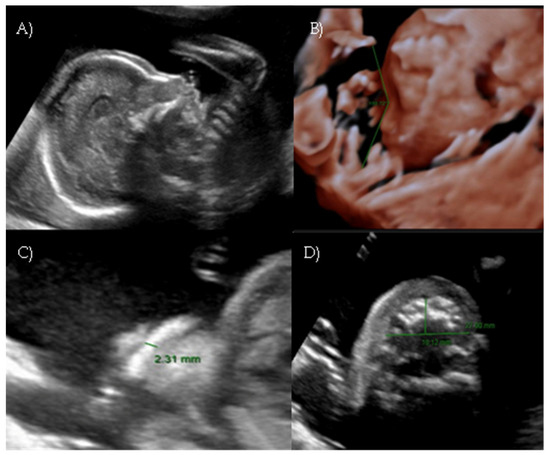

A targeted second-level ultrasound at our center revealed a flat fetal facial profile: the nasal-frontal angle measured 151.50°, and flattening of the curvature of the maxillary alveolar processes was noted (Width: 26.44 mm, Cut-off at 21 weeks: 23.1 mm [6]) suggestive of Binder-type maxillonasal dysplasia, moderate monolateral calyceal-pelvic dilatation of 8 mm in the left kidney, two echogenic intracardiac foci, and long bone biometry at the lower limits of normal (Figure 3 A–C).

Figure 3. Case 3. (A) Flat fetal profile, 3D reconstruction. (B) Nasal-frontal angle: 151.50°. (C) Flattening of the curvature of the maxillary alveolar processes. Width: 26.44 mm.